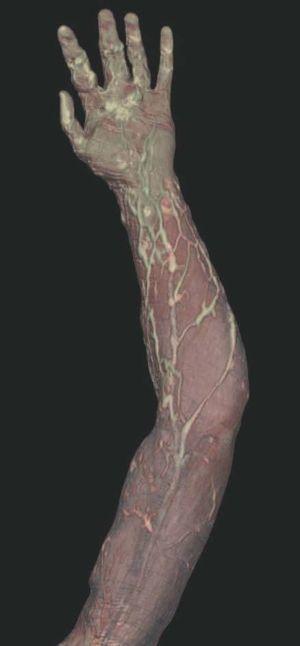

Hoy en día la utilización de los nuevos equipos TC multicorona y RM permiten la adquisición de imágenes con gran rapidez, pudiendo realizar reconstrucciones multiplanares de gran calidad, así como estudios angiográficos no invasivos13,23. Recientemente hemos estudiado 16 pacientes con síndrome de Klippel-Trenaunay mediante una venografía tomografía computarizada multicorte (TCM) o una venografía resonancia magnética tridimensional (RM-3D), utilizando imágenes axiales convencionales, reconstrucciones multiplanares (RMP), proyecciones de máxima intensidad (PMI) e imágenes tridimensionales (figs. 1-3). Las imágenes axiales convencionales fueron de utilidad para evaluar el tejido blando y el hueso y permitieron localizar el sistema venoso profundo y los vasos anómalos superficiales, determinando su relación con estructuras adyacentes. Las imágenes axiales, RMP y PMI fueron empleadas para trazar el origen, trayecto y extensión de las malformaciones venosas. Las imágenes de la superficie cutánea permitieron evaluar la localización y la extensión de la mancha en vino de Oporto y demostrar la hipertrofia de la extremidad. Las reconstrucciones tridimensionales permitieron demostrar las varicosidades y el origen y trayectoria de los vasos aberrantes (figs. 4 y 5). Ninguno de los pacientes requirió otra técnica complementaria invasiva (flebografía convencional) para confirmar el diagnóstico y planificar las estrategia terapéutica24.

Figura 1. Mujer de 16 años con malformación venosa extensa en extremidad superior izquierda y afectación de predominio distal.

Figura 2. En angio-tomografía axial computarizada (TAC) se aprecia una correlación de los vasos superficiales con la afectación clínica.

Figura 3. En un detalle de la angio-tomografía axial computarizada (TAC) se observa la relación de los vasos con estructuras internas.